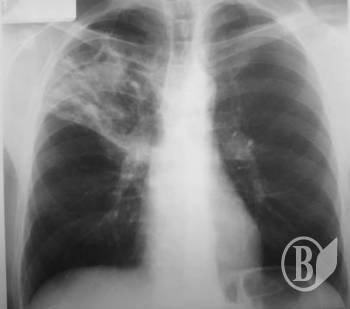

З 1995 року в Україні і досі залишається актуальною проблема інфекційних захворювань. Особливо щодо туберкульозу. Нажаль, ця проблема не оминула дітей.

До дитячого відділення Обласного протитуберкульозного диспансеру потрапляють малі пацієнти в разі інфікування туберкульозом, з вогнищ туберкульозної інфекції, групи підвищеного ризику захворювання та хворі на туберкульоз.

За статистикою в Чернігівській області не така велика захворюваність на туберкульоз серед дітей ― 4,3 випадки захворювання на 100 тис. дитячого населення за рік( це 14-15 захворювань за рік), а по Україні ― 8,9 випадків захворювання на 100 тис. дитячого населення.

На обліку в області перебуває 2376 дітей з латентною туберкульозною інфекцією, які виявляються за допомогою щорічної туберкулінодіагностики і потребують проведення обстеження та контрольованої хіміопрофілактики з метою попередження розвитку захворювання.